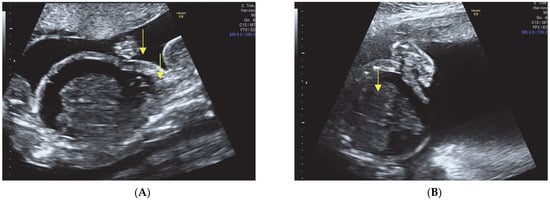

- Hypomineralization of the skull bones.

- Enlarged head and small face.

- Narrow thorax with evidence of pulmonary hypoplasia.

- Multiple rib fractures.

- Presence of fetal hydrops, characterized by ascites, pleural effusion, and subcutaneous edema.